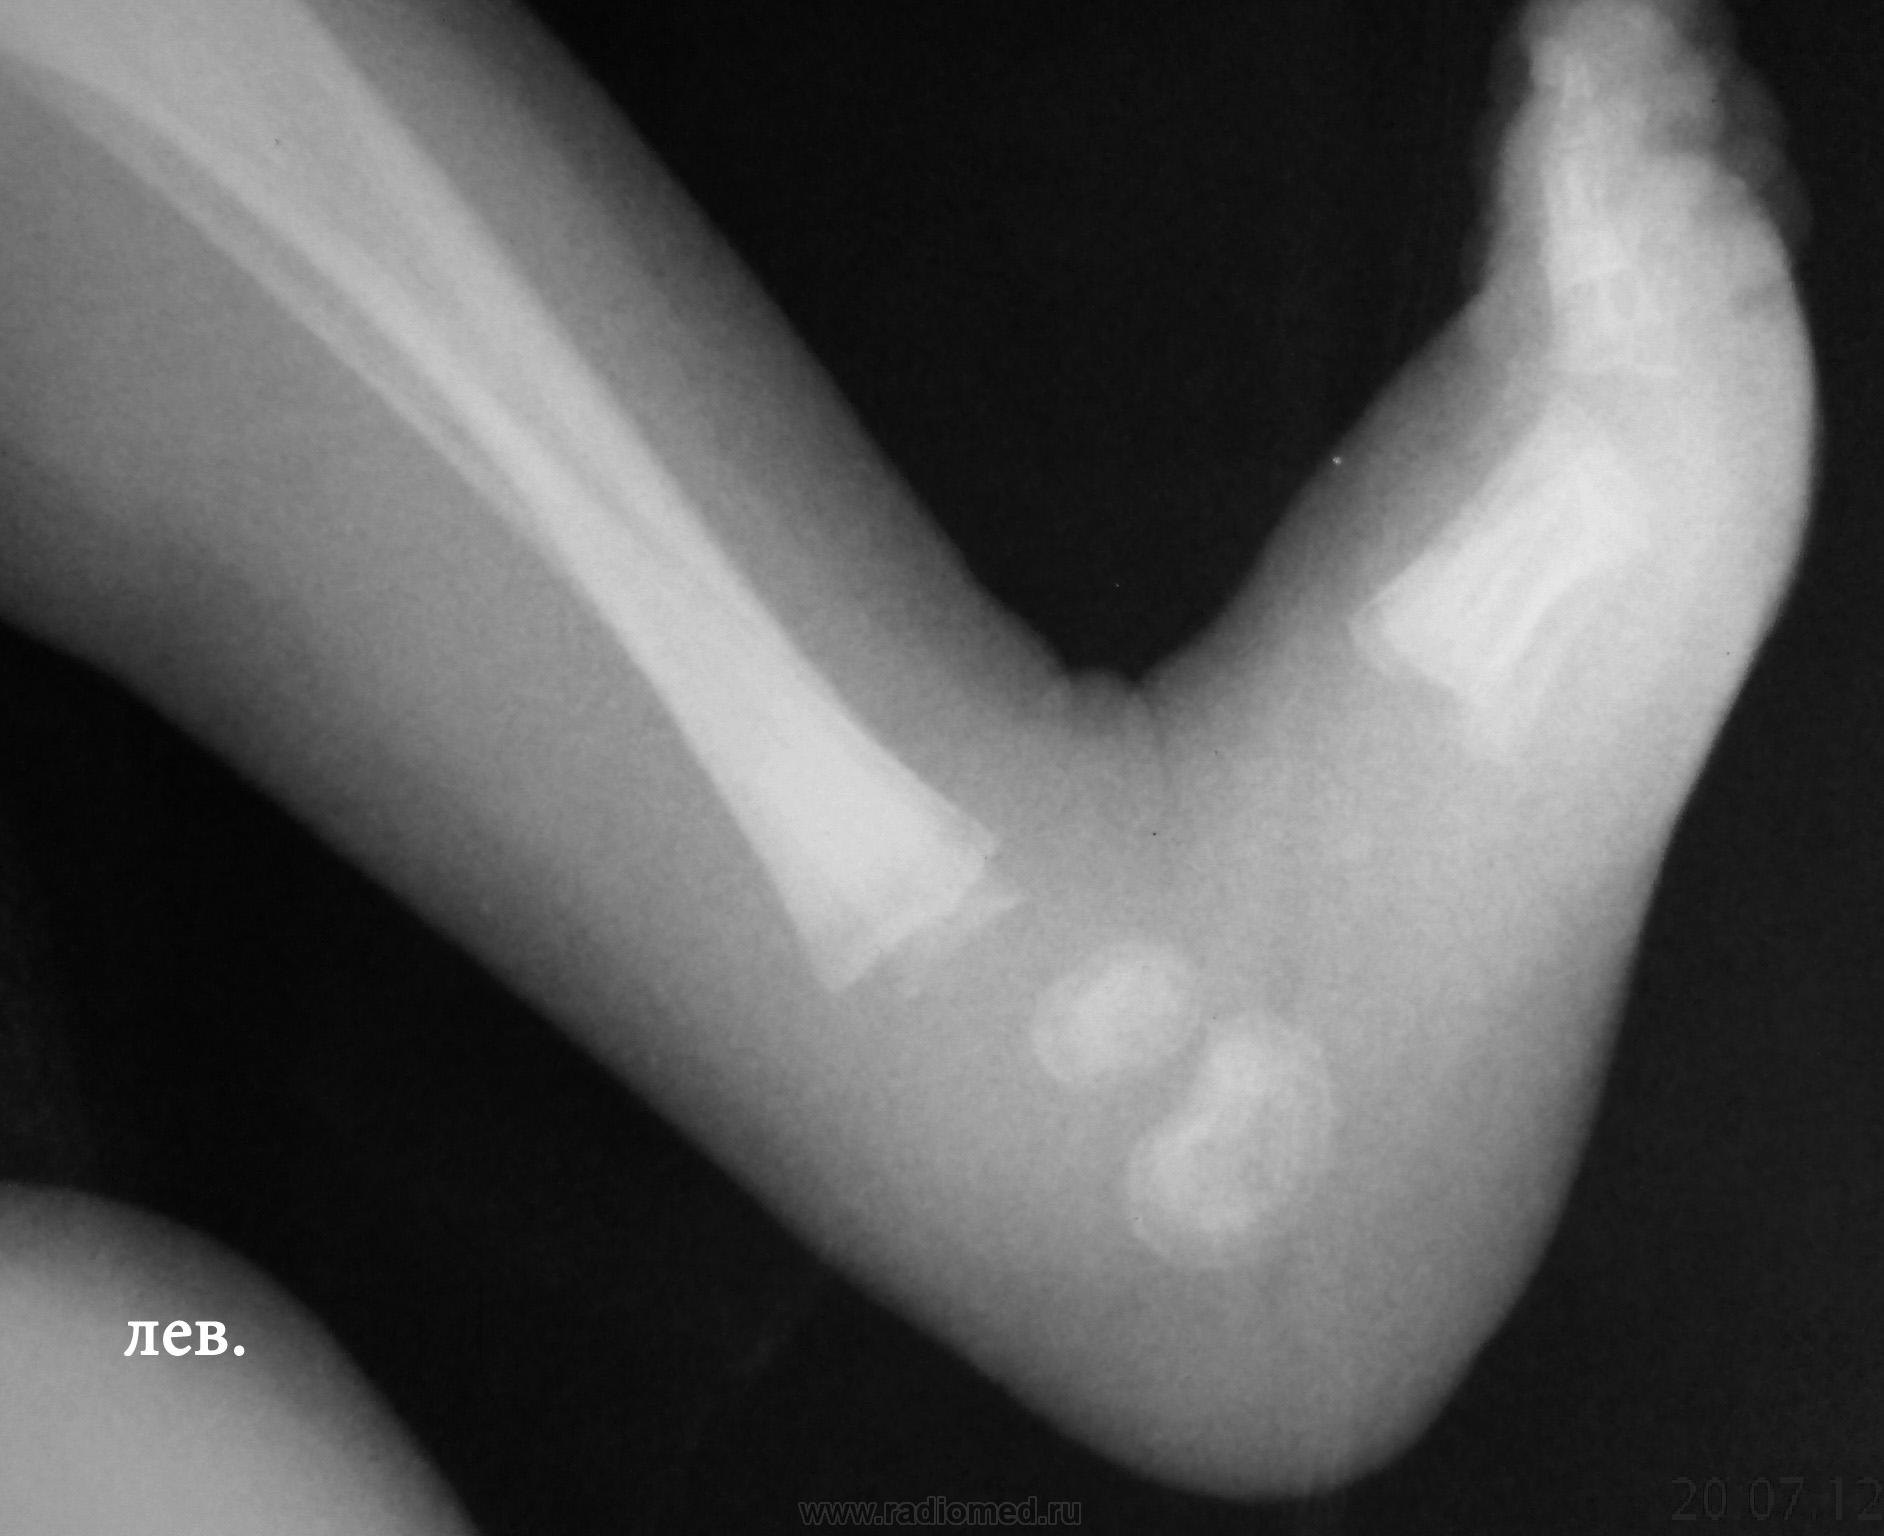

Ребенку 2-3 недели, лежит у нас по поводу остеомиелита. Дней 7 назад - появились отек, болезненность левого голеностопа, про анализы, к сожалению, ничего сказать не могу. Получил курс антибиотиков, отек спал.

В проксимальных метафизах большеберцовых - такие же полоски.

Давно не встречалась с врожденным костным сифилисом, лет 10, позабылось все (раньше, в другой больнице, видела его достаточно часто), но что могу сказать - полосы просветления в метафизах (а также полосатость ядер окостенения пяточной и таранной костей) встречаются не только при сифилисе, часто видела их у здоровых недоношенных;  при сифилисе, кроме этих полос, должно быть расширение и зазубренность зон предварительного обызвествления, симметрично в костях голеней и предплечий, клинически, обычно, не проявляется, только при третьей стадии остеохондрита, когда появляются псевдопараличи Парро - появляется припухлость, отек, ограничение движений, и это также с обеих сторон. Здесь мне видится нечеткость метафиза малоберцовой кости слева, скорее всего, обычный остеомиелит. Конечно, анализ на сифилис, все-равно, заказать надо.

Здесь мне видится нечеткость метафиза малоберцовой кости слева, скорее всего, обычный остеомиелит. Конечно, анализ на сифилис, все-равно, заказать надо.

К малоберцовке тоже придрался, тем более и клиника именно там была.